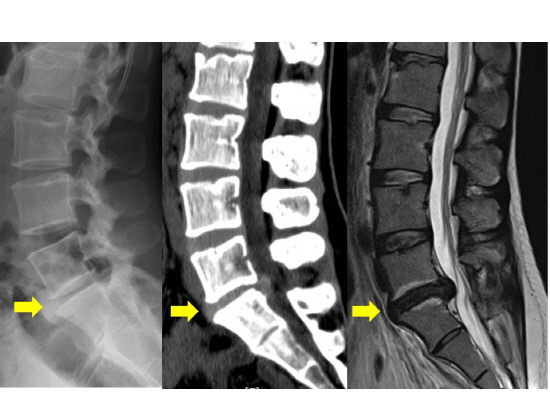

X-Ray 검사는 척추 질환을 진단하는 데 가장 기본적으로 쓰이는 검사로서 척추의 전반적인 형태를 한 눈에 볼 수 있습니다. 뼈의 모양을 여러 각도에서 촬영하므로 척추의 구조적인 형태를 관찰하기 쉽습니다. 척추측만증이나 척추분리증 등의 질환은 X-Ray 검사만으로도 확진이 가능합니다. X-Ray 검사를 통해 아래 그림처럼 뼈의 간격을 보고 퇴행성 진행정도를 먼저 파악하는 것이 중요합니다. 다만 디스크 질환은 다릅니다. 척추 뼈의 간격이나 퇴행성 진행 정도로 디스크의 가능성은 알 수 있지만, 디스크가 보이지 않기 때문에 디스크가 발생한 정확한 부위나 진행 정도를 알아내지 못해 디스크라는 확진을 내리기엔 부족합니다.

허리디스크 확진을 받으려면 엑스레이만 가지고는 안 되고, CT나 MRI 검사를 반드시 시행해야 합니다. 엑스레이를 찍은 후 허리디스크 진단을 받으면 대개 약 복용과 물리치료를 하게 되는데요. 치료를 1~2주 이상 시행해도 통증에 전혀 호전이 없거나 견딜 수 없을 정도로 극심한 통증을 느낀다면, 참지 말고 그 즉시 정밀검사를 받으러 가세요.

대부분의 허리디스크 탈출이나 파열은 CT 검사를 통해 진단할 수 있지요. 하지만 CT 검사를 시행해도 허리디스크를 제대로 진단하지 못하는 경우가 종종 있습니다. 또한 CT 검사는 허리디스크에 눌린 신경이 어떤 상태인지 정확하게 알아낼 수 없다는 단점을 가지고 있습니다.

필자가 MRI를 환자분들께 권해드리는 이유가 여기에 있습니다. MRI는 허리디스크를 가장 정밀하게 진단하는 검사입니다. MRI 검사를 하면 허리디스크 탈출 또는 파열 여부와 신경의 상태를 가장 정확하게 진단할 수 있습니다. CT 검사에서 놓쳤던 부분들까지 MRI는 잡아준답니다. MRI는 고가의 검사이니, 환자분들이 머뭇거리게 되는 게 당연합니다.